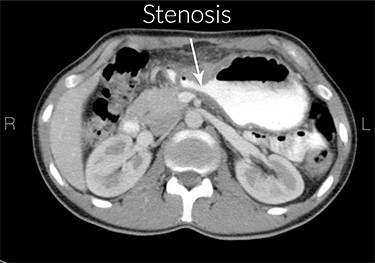

CT scan report

Increased gastric wall thickness was observed with emphasis on antropyloric region and the lesser curvature with maximum thickness of 21 mm accompanied by fat stranding around the same areas. Evidence of partial stenosis with mild dilatation of stomach was seen. Contrast agent has penetrated through the distal region and no leak of contrast agent is observed. Liver, spleen and the pancreas looked normal. No apparent paraaortic lymphadenopathy was observed. No free fluid was observed in the abdomen and the pelvic cavity (Figs 1 and 2).

Stenosis of the gastric outlet. R means right and L means left.